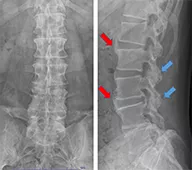

Vol.07[腰痛(動作、座位で悪化し、臥位で軽快する)]

1年前より特に誘引なく腰痛を繰り返すようになった。特に座位時の腰痛が悪化し、デスクワークができなくなったため、当科脊椎外来を紹介受診となる。